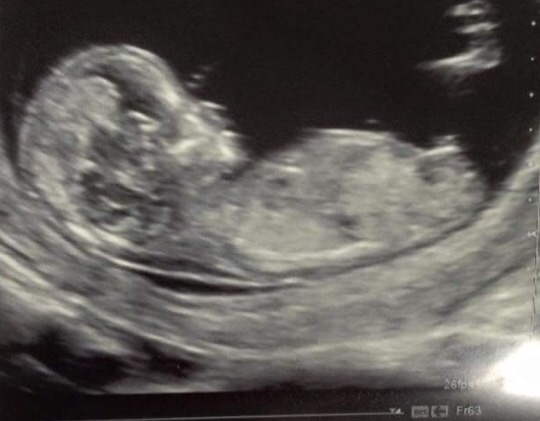

This is my little one at 12+5 weeks, I'd love to hear your guesses of boy or girl and why. Thank you xx

I think boy because it's stacked. Although it is quite parallel to the spine (girl). But my guess would still go to boy.

Looks like my girls nub at 11+6 but guess could go either way x

Boy and because its stacked! And it looks like its rising up. Good luck what are you hoping for? Xx